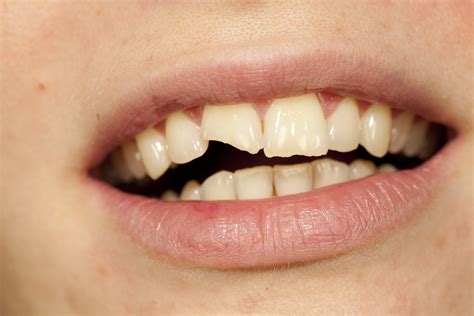

Finding a small line on your tooth enamel or feeling a sudden sharp pain when you bite down can be an alarming experience. Many people notice cracking in teeth and immediately assume the worst, fearing a total tooth loss. While dental fractures are common, they exist on a broad spectrum ranging from harmless cosmetic lines to deep structural breaks that require urgent intervention. Understanding what causes these fissures, how to identify the symptoms, and when to see a dentist is essential for maintaining your long-term oral health.

Unlike a cavity that might show up as a dark spot on an X-ray, cracking in teeth is often elusive. You might not see a crack with the naked eye, but you will likely feel it. Pay attention to these warning signs: